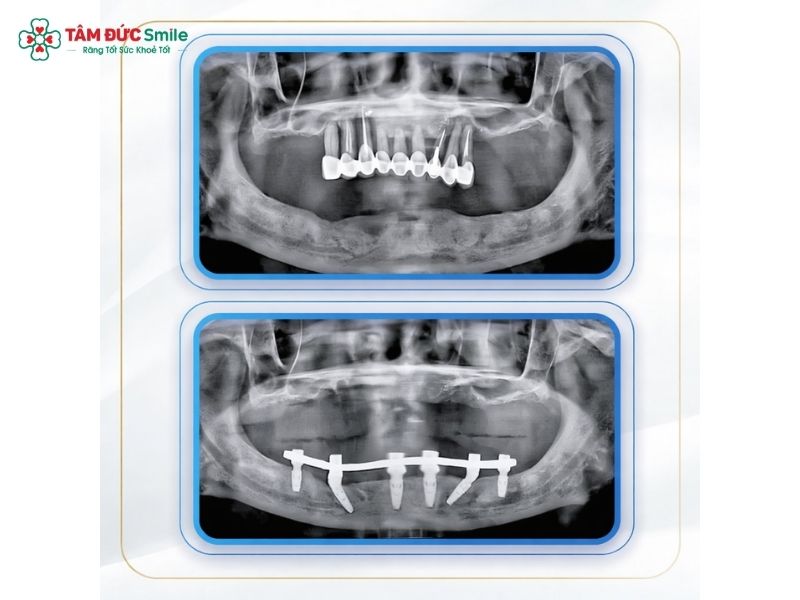

3.2 Surgical Placement of Six Implants

During surgery:

- Six titanium dental implants are placed into the jawbone at carefully calculated angles.

- Angled placement maximizes bone contact and enhances implant stability and support.

- Local anesthesia or sedation ensures patient comfort.

This strategic positioning is a key advantage of All-on-6 implants, allowing for strong anchorage even in areas with limited bone.